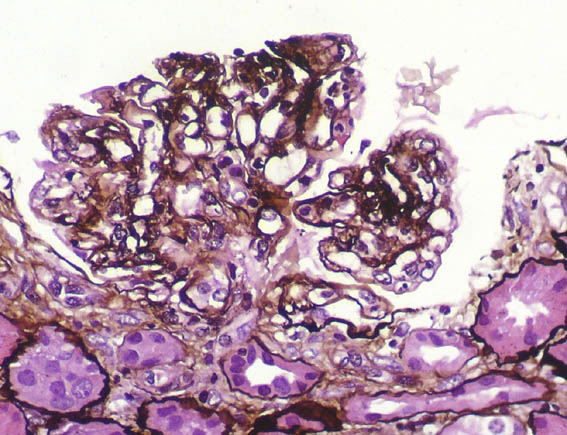

PAS,

X400.